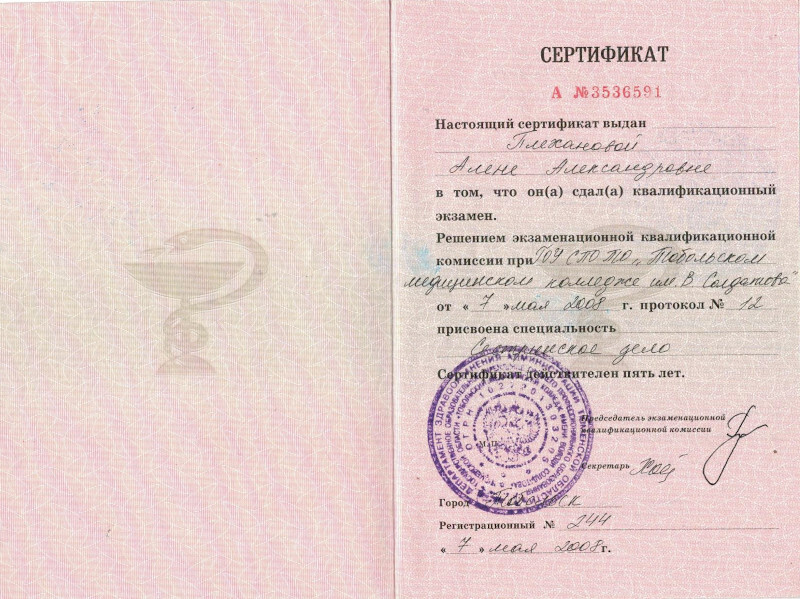

Сертификаты на технологии холодной плазмы